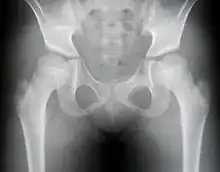

Radiographie d'un cas de dysplasie de hanche avant opération.

Cette maladie se manifeste d'abord par des douleurs articulaires des hanches apparaissant souvent dans l'enfance. La marche est progressivement perturbée et aboutit à une infirmité. L'état général est bon et il n'existe aucune manifestation extra articulaire. Le signe radiologique majeur est l'aplatissement de l'épiphyse de la tête fémorale.